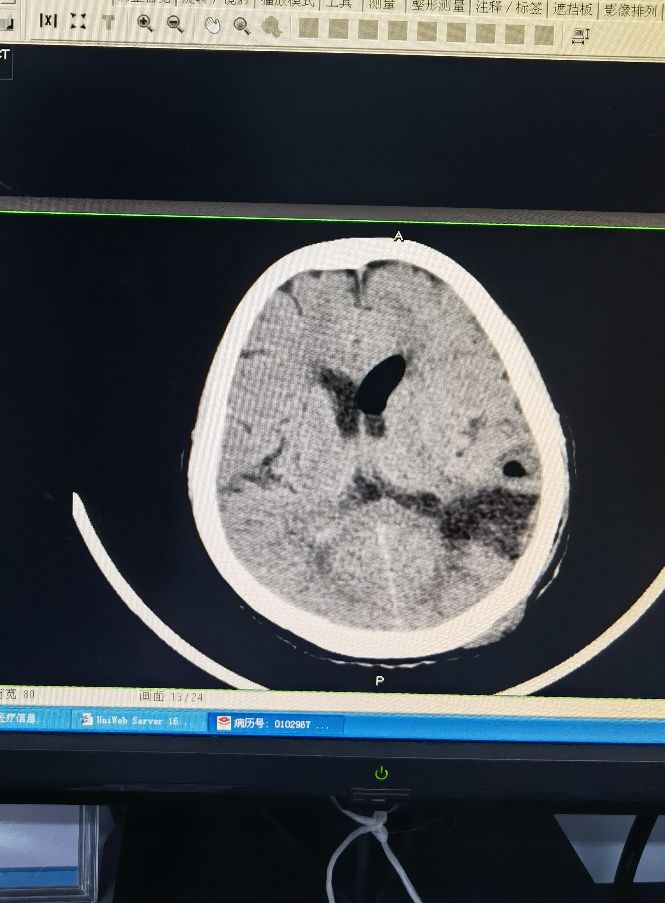

硬通道脑室引流术 (颅内出血保守治疗又出血)

硬脑膜外血肿引流,高压氧治疗颅内出血